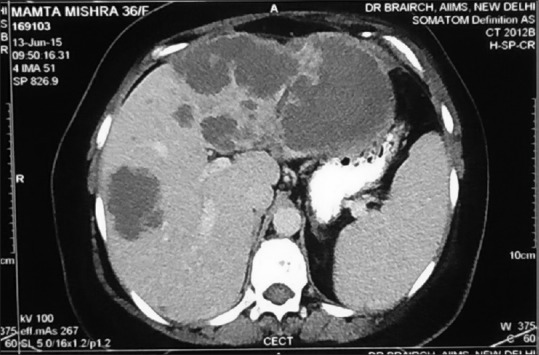

Clinically, she was pale, icteric, had bilateral pedal edema and dullness on percussion at the left base. Her Eastern Cooperative Oncology Group performance status (PS) was 3. She had a hemoglobin of 4.3 g/dl, total leukocyte count 14,100/mm3, platelet 135,000/mm3. Serum creatinine was 0.5 mg/dl. Serum bilirubin was 4.46 mg/dl (conjugated = 2.49 mg/dl). Serum albumin = 2.54 g/dl, aspartate aminotransferase/alanine aminotransferase = 128/82 U/L, serum alkaline phosphatase = 759 U/L. On evaluation, her positron emission tomography computed tomography (CT) scan showed left-sided pleural effusion with passive collapse of left lower lobe, no ascites, but multiple hypodense nodules (largest 10 cm) in an enlarged liver [Figure 1]. There were no significant uptake on FDG -PET Scan or DOTANOC -PET Scan. There were no intrahepatic biliary radicle dilatation. There were ill-defined lytic lesions in multiple visualized bones.

| Figure 1:Computed tomography scan of abdomen of the patient in June 2015, showing multiple large hypodense nodules of metastatic angiosarcoma in both lobes of liver